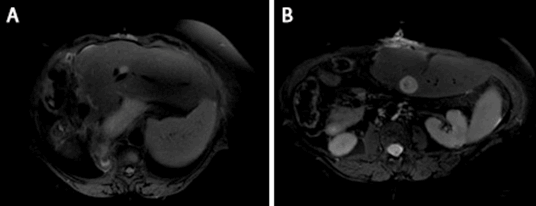

Abdominal CT 65 days after surgery demonstrated no new evidence of malignancy. Gemcitabine and cisplatin were initiated at 96-day follow up as planned adjuvant treatment. The patient’s lipase had increased to 2,595 U/L by this point, raising concern for occult metastasis. Her panniculitis had completely resolved. Follow-up MRI 158 days after surgery confirmed two new liver lesions, measuring 2.6 cm and 1.3 cm (Figure 6). Cisplatin was replaced with oxaliplatin due to rising creatinine at this time. Gemcitabine and oxaliplatin were discontinued in favor of olaparib, an inhibitor of the enzyme poly ADP ribose polymerase (PARP), 223 days after surgery.

Figure 6. Postoperative imaging: magnetic resonance (MR) imaging of abdomen with contrast demonstrating two metastatic lesions in the left lobe of the liver located in segment two (A, 1.1 cm) and segment three (B, 2.7 cm)